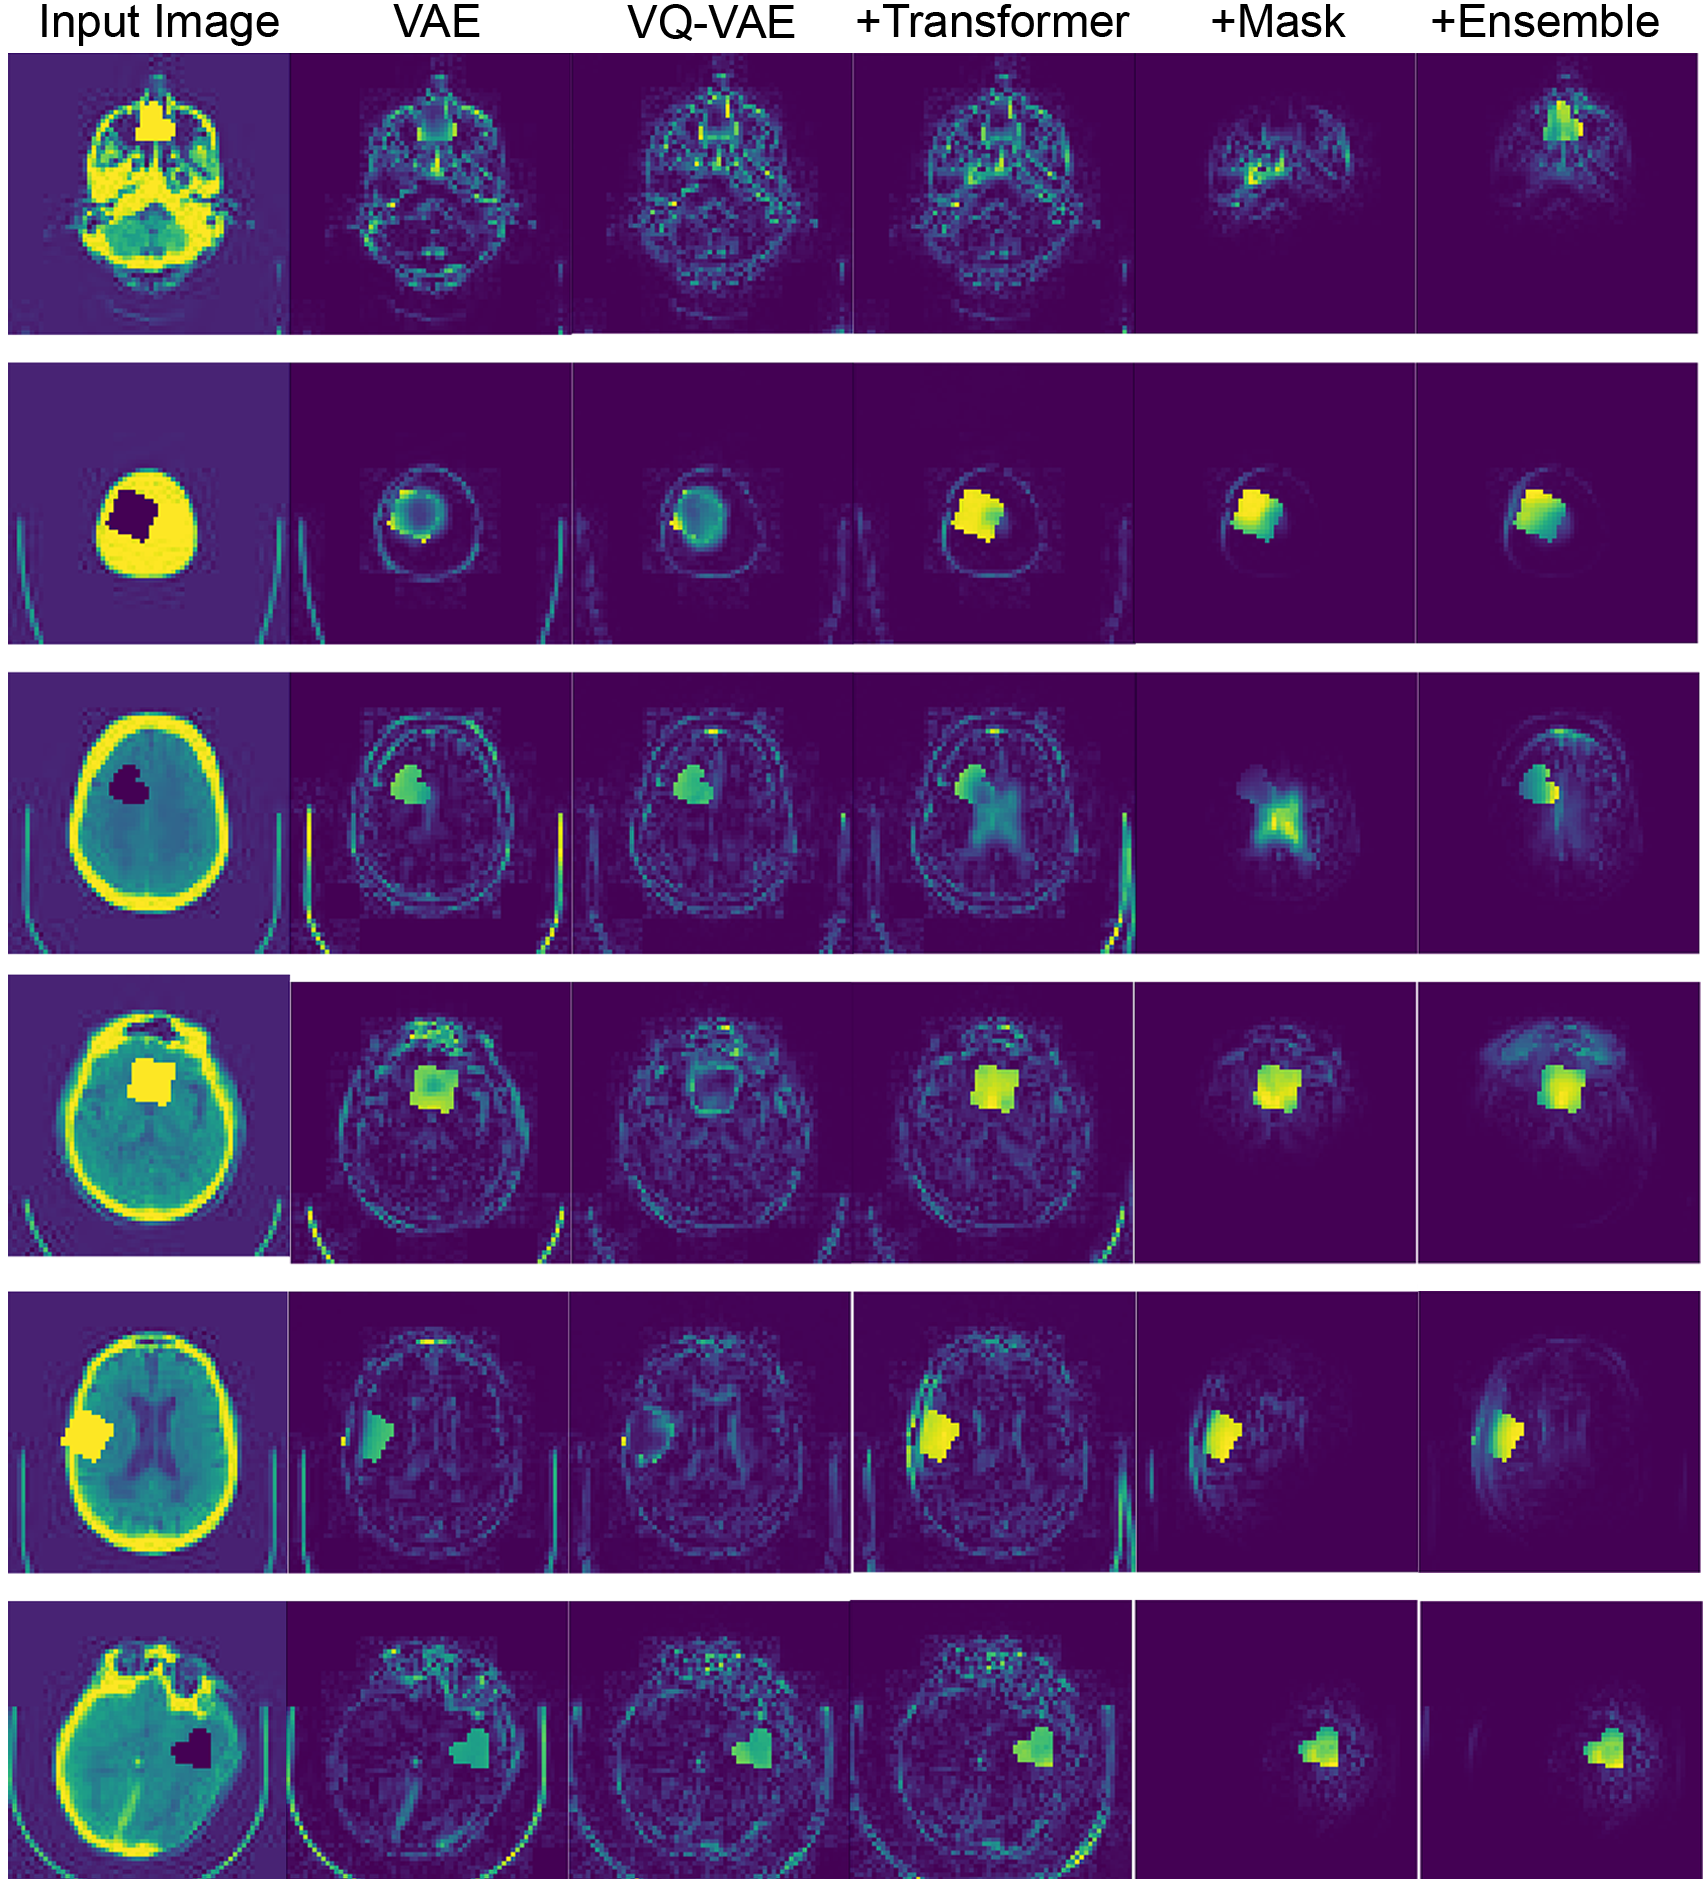

4.1 Experiment #1 – Anomaly Segmentation on Synthetic Data

To assess anomaly segmentation performance on synthetic data, we utilized a subsample of the MedNIST dataset111Available at \urlhttps://github.com/Project-MONAI/tutorials, where we used the images of the “HeadCT” category to train our models. Our test set comprised 100 images contaminated with sprites Matthey et al. (2017), thus producing ground-truth abnormality masks. We measure the performance using the best achievable DICE-score (), which constitutes a theoretical upper-bound to a model’s segmentation performance and is obtained via a greedy search for the residual threshold which yields the highest DICE-score on the test set. We compared our results against state-of-the-art autoencoder models based on the architectures proposed in the Baur et al. (2020a) comparison study, assessed in the same manner. We also performed an ablation study of the proposed method demonstrating the values of each contribution.

As presented in \tablereftab:syntseg, the models based only on autoencoders had a highest of 0.533 (VAE). We observed an improvement in performance when using the transformer to in-paint the latent space, changing the VQ-VAE only performance from 0.457 to 0.675. The spatial information in the resampling mask also contributed by attenuating the impact of the blurry reconstructions (Figure LABEL:fig:exp1), achieving a 0.768 score. Finally, the variability of the generative models with different orderings gave another boost in performance (for 8 different raster ordering models =0.895).

fig:exp1

Our method showed a better performance than the autoencoder approaches from the literature in all datasets (\tablereftab:syntseg and Figure LABEL:fig:exp3). Compared to the numbers in Baur et al. (2020a), our autoencoder-based models got a lower performance on the common dataset (MSLUB dataset), where they achieved an DICE score of 0.271 with the AE (dense), 0.154 with the AE (spatial), and 0.323 with the VAE (dense). We believe that the discrepancy comes mostly from the significant post-processing of the Baur et al. (2020a) work as presented in Table 8 of this reference. Differences might also arise from the difference in resolution, as the DICE score is not invariant to resolution.

fig:exp3

Appendix B More Residuals maps from Experiment #1

fig:appendixb

Appendix C More Residuals maps from Experiment #3

fig:appendixc